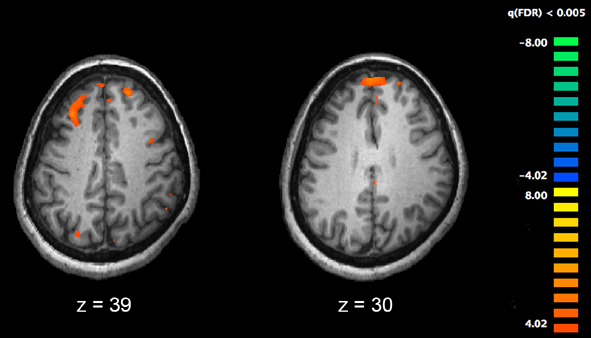

For the study, published in the journal Cerebral Cortex, the researchers followed 120 students. Each of them completed a series of mental health questionnaires and underwent a type of non-invasive brain scan called functional Magnetic Resonance Imaging (fMRI) while engaged in tasks meant to activate specific regions of the brain.

The researchers asked each participant to answer simple memory-based math problems to stimulate the dorsolateral prefrontal cortex.

The participants also viewed angry or scared faces to activate a region of the brain called the amygdala, and played a reward-based guessing game to stimulate activity in the brain’s ventral striatum.

“We found that if you have a higher functioning dorsolateral prefrontal cortex, the imbalance in these deeper brain structures is not expressed as changes in mood or anxiety,” Hariri said. (AGENCIES)